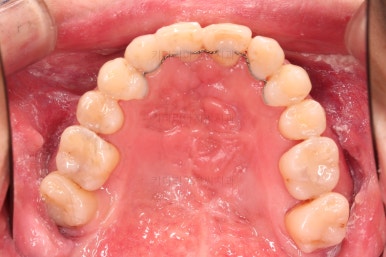

교정 10개월째인데, 악궁형태 많이 좋아졌고, 가지런한 느낌도 많이 좋아졌습니다.

6. 마무리와 치료종료

부산구순구개열교정 종료 시의 입안의 모습입니다.

위아랫니 정렬이 잘 되었고, 치아 갯수가 위아래가 다르지만 교합도 나쁘지 않게 마무리가 되었습니다.

대문니 2개가 예후가 안좋긴 하나 양옆 치아들과 유지철사로 부착해 두어 최대한 오래 조심히 써보기로 했습니다.